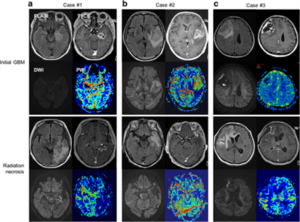

CASE LÂM SÀNG Điều trị bệnh nhân ung thư phổi di căn não giai đoạn muộn tại Trung tâm Y học hạt nhân và Ung bướu-Bệnh viện Bạch Mai PGS.TS. Phạm Cẩm Phương1,2, GS.TS. Mai Trọng Khoa1,2, Sinh viên Nguyễn Thị Hải Anh,2 1Trung tâm Y học hạt nhân và...